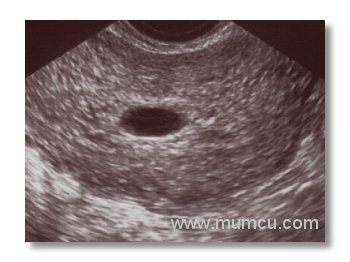

5 haftalık gebelikte gestasyonel kese

Vajinal ultrasonografi